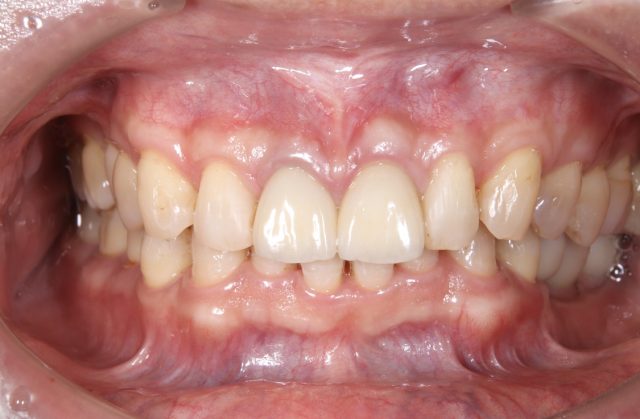

前歯の被せ物のやり替え治療(オールセラミック)

Before

After

| 診断名 | 前歯の審美補綴治療 |

| 年齢・性別 | 40代・男性 |

| 治療期間・回数 | 半年/10回 |

| 治療方法 | 審美補綴治療(オールセラミック) |

| 費用 | セラミックス補綴(1歯):165,000円(税込み) 歯周外科(1ブロック):110,000円(税込み) |

| デメリット・注意点 | 保険が適用できないため自費診療になる。 セラミックスインレー・クラウンに強い力がかかると割れてしまう恐れがあるため、歯ぎしりや食いしばりが癖になっている患者様にはおすすめできない場合がある |